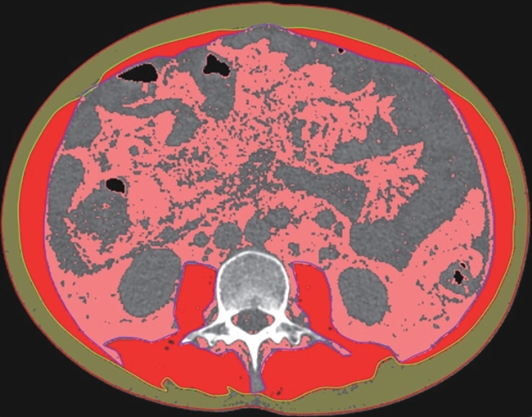

目的 本文旨在肌肉脂肪浸润的基础上,利用分层分析的方法将肌肉内部按照不同的密度范围划分成不同的亚分区,进一步研究肌肉密度改变对原位肝移植术(OLT)后并发症(Clavien-Dindo≥Ⅲ)的影响。 方法 回顾性分析2013年5月—2020年9月于吉林大学第一医院行OLT的145例患者,以患者腰3椎体水平最大层面的CT平扫图像作为原始数据,利用Neusoft Fatanalysis软件对图像进行相关肌肉参数的测量。符合正态分布的计量资料组间比较采用成组t检验;不符合正态分布的组间比较采用Mann-Whitney U秩和检验。计数资料组间比较采用χ2或Fisher检验。利用RIAS软件进行临床特征提取及分析建模,分别建立逻辑回归(LR)、支持向量机(SVM)、随机森林(RFC)3种机器学习模型,并绘制不同模型的受试者操作特征曲线(ROC曲线)、校正曲线、决策分析曲线,计算ROC曲线下面积(AUC)、灵敏度、特异度、精确率、F1分数、准确率。 结果 采用肌肉分层分析前的7种临床特征建立LR-C、SVM-C、RFC-C 3种机器学习模型,其中RFC-C模型测试集的AUC值为0.803、灵敏度0.588,特异度0.778。采用肌肉分层分析后的16种临床特征建立的LR-CS、SVM-CS、RFC-CS模型中,LR-CS及SVM-CS模型测试集的AUC值较高,均为0.852,灵敏度分别为0.765、0.706,特异度分别为0.889、0.926,通过对比肌肉分层分析前后各模型测试集的AUC、灵敏度、特异度、精确率、F1分数、准确率后发现,肌肉分层分析后预测模型的参数均有所提升。通过对比各预测模型的决策分析曲线和校正曲线,发现LR-CS及SVM-CS模型对于预测OLT患者术后并发症(Clavien-Dindo≥Ⅲ)具有良好效能。 结论 在肌肉脂肪浸润的基础上,利用分层分析的方法将肌肉内部按照不同的密度划分成不同子区,对于OLT患者术后并发症有一定预测价值。 Abstract:Objective To divide the muscle into different subzones according to different density ranges using the stratified analysis on the basis of myosteatosis, and to investigate the effect of muscle density changes on complications (Clavien-Dindo grade ≥Ⅲ) after orthotopic liver transplantation (OLT). Methods A retrospective analysis was performed for the medical records of 145 patients who underwent OLT in The First Hospital of Jilin University from May 2013 to September 2020, and with the plain CT scan images of the largest level of lumbar 3 vertebrae of each patient as the original data, Neusoft Fatanalysis software was used to measure related muscle parameters. The independent-samples t test was used for comparison of normally distributed continuous data between two groups, and the Mann-Whitney U test was used for comparison of non-normally distributed continuous data between two groups. The chi-square test or Fisher test was for comparison of categorical data between two groups. RIAS software was used to extract clinical features and perform analysis and modeling, and three machine learning models of logistic regression (LR), support vector machine (SVM), and random forest (RFC) were constructed. The receiver operating characteristic (ROC) curve, the calibration curve, and the decision curve were plotted for each model to calculate the area under the ROC curve (AUC), sensitivity, specificity, precision, F1 score, and accuracy. Results The three machine learning models of LR-C, SVM-C, and RFC-C were established based on the 7 clinical features before muscle stratification analysis, among which the RFC-C model had an AUC of 0.803, a sensitivity of 0.588, and a specificity of 0.778 in the test set. Among the models of LR-CS, SVM-CS, and RFC-CS established based on the 16 clinical features after muscle stratification analysis, the LR-CS and SVM-CS models had an AUC of 0.852 in the test set, with a sensitivity of 0.765 and 0.706, respectively, and a specificity of 0.889 and 0.926, respectively. Comparison of the AUC, sensitivity, specificity, precision, F1 score, and accuracy of each model in the test set before and after muscle stratification analysis showed that there were improvements in the parameters of the predictive model after muscle stratification analysis. Comparison of the decision curves and calibration curves of each predictive model showed that the LR-CS and SVM-CS models had good efficacy in predicting postoperative complications (Clavien-Dindo grade≥Ⅲ) in OLT patients. Conclusion On the basis of myosteatosis, the division of the muscle into different subzones according to different densities using the stratified analysis has a certain value in predicting postoperative complications in patients with OLT. -